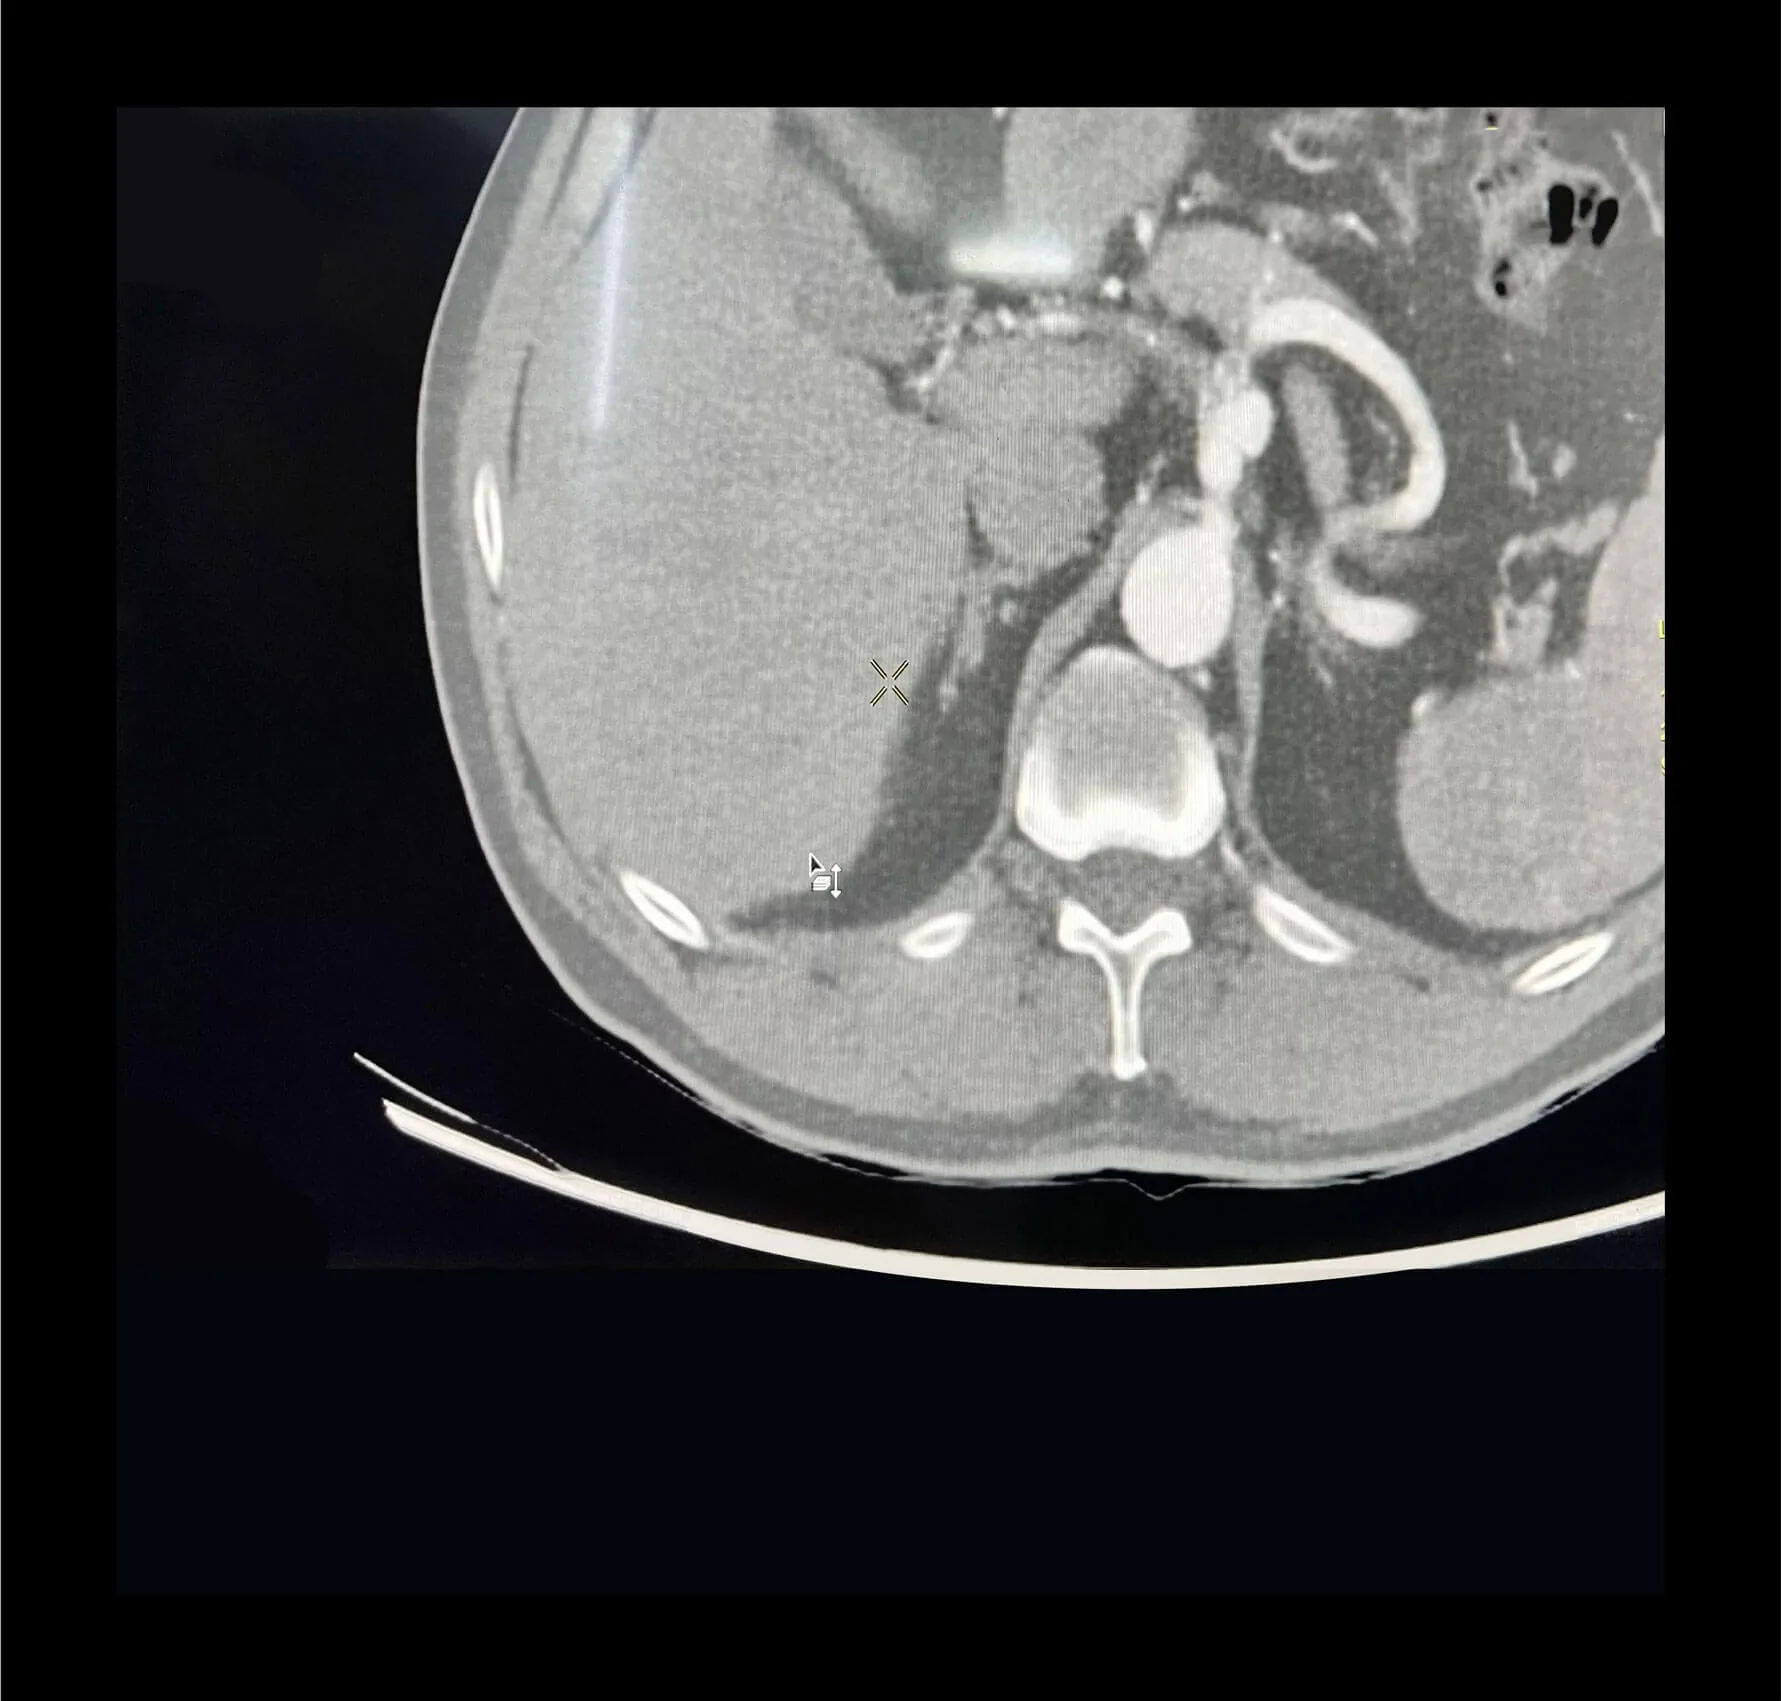

Some tests such as duplex and CT angiography can confirm its presence.

Most of these aneurysms require treatment when they measure over 2 cm.